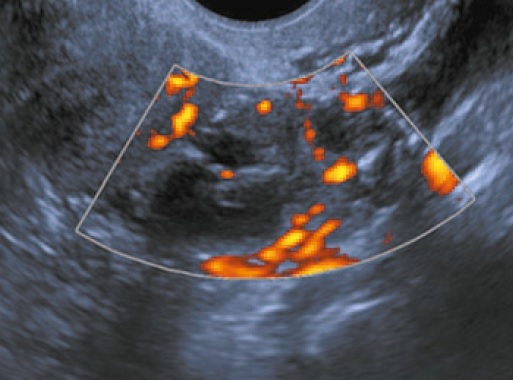

Новообразования, отнесенные к 1-й группе, характеризовались типичными ультразвуковыми признаками многокамерного кистозного образования с тонкими перегородками и пристеночными разрастаниями в виде сосочковых структур разного диаметра. При использовании цветового допплеровского картирования и энергетического допплера более чем у 1/2 из них в солидном компоненте картировались единичные сосудистые локусы (рис. 2).

Рис. 2. Трансвагинальное УЗИ. При цветовом допплеровском картировании определяются сосудистые локусы в сосочковых разрастаниях.

Fig. 2. Transvaginal ultrasound. The color doppler imaging demonstrates the vascular pattern in the papillary growth pattern.